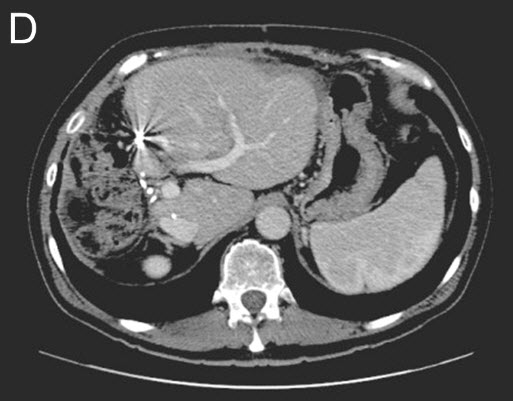

![]() |

| (D) Stage II - Second Surgery: The right liver and tumors are removed. CT-Scan shows additional growth (hypertrophy) of the remaining liver remnant. |